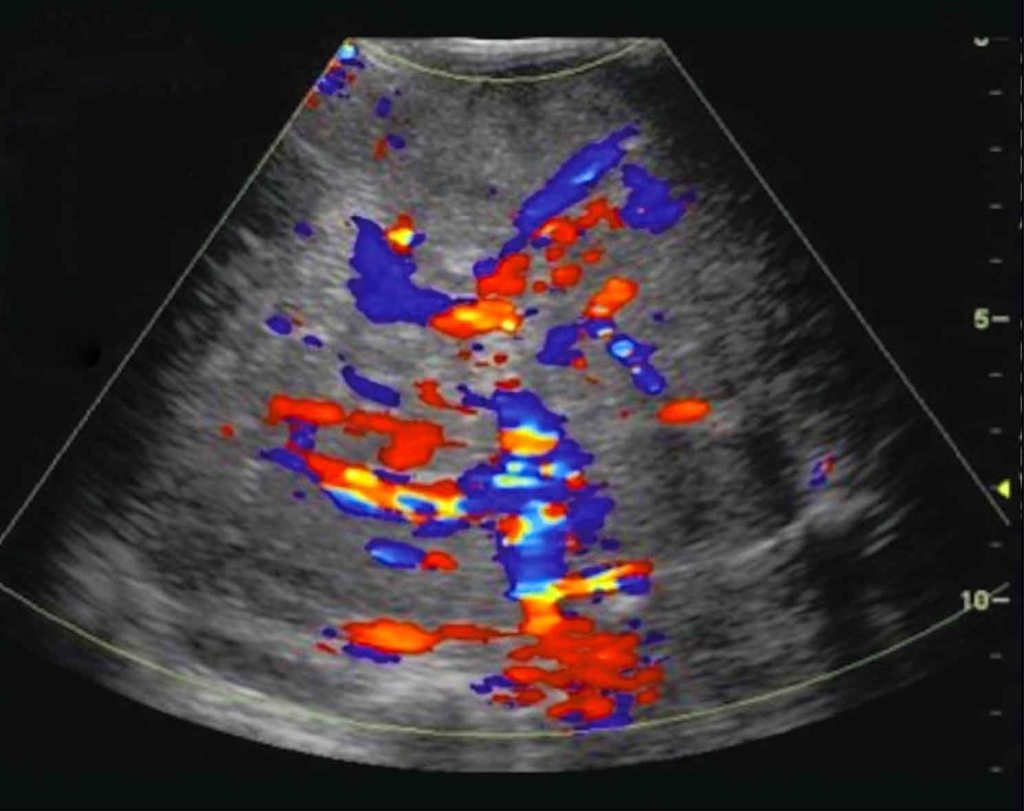

L’ecografia è un sistema di indagine medica che non utilizza radiazioni ionizzanti, ma ultrasuoni ed è perciò innocua. In virtù della sua ampia diffusione e della assenza di controindicazioni questa metodica viene considerata come esame di base ed è utilizzata sempre di più nella quotidiana pratica clinica.

L’ecografia può inoltre essere utilizzata per procedure diagnostiche e terapeutiche mini invasive, come il drenaggio di una raccolta infetta o la biopsia di un nodulo.